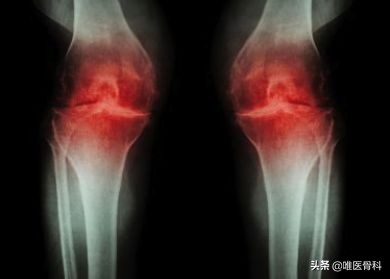

骨关节炎是怎么回事?

膝关节骨关节炎是骨科常见的慢性疾病,其发病原因迄今为止尚未完全明了,它的发生发展是一种长期、慢性、渐进的病理过程;

一般认为是多种致病因素包括机械性和生物性因素的相互作用所致。

其中年龄是主要的高危因素,其他包括外伤、肥胖、遗传、炎症、代谢等。